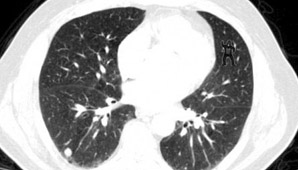

Estados Unidos, 13 de febrero.- Mira la foto de arriba. ¿Ves algo raro?. Un estudio realizado por un hospital de Boston reveló que el 83% de los radiólogos consultados no pudo ver al animal en las imágenes.

En el estudio, los investigadores les pidieron a los me´dicos que dijeran lo que veían en las tomografías de cinco pacientes con cáncer de pulmón. En las primeras cuatro exploraciones de pacientes no se notó nada raro, pero oculto en la pila de 239 imágenes de la quinta paciente había cinco tomografías consecutivas que muestran a un gorila bailando.

En efecto, para ayudar a su investigación la primera de esas imágenes fue con el 50% del gorila transparente, la segunda con el 75% del animal visible y la tercera con el simio plenamente observable, antes de “desaparecer” de nuevo al 50% en las últimas dos exploraciones.

Pero sólo cuatro de los 24 radiólogos informaron haber visto el gorila durante la prueba, en la cual los investigadores utilizaron la tecnología de seguimiento de los ojos para ver donde los investigadores habían estado buscando y si se pasa sobre el gorila en la tomografía, según publica el diario británico Daily Mail.

"La mayoría de ellos miró directamente a los gorilas durante largos períodos de tiempo, pero simplemente no pudieron verlos”, aseguró Trafton Drew, quien dirigió el estudio en el mencionado centro de salud de Boston.